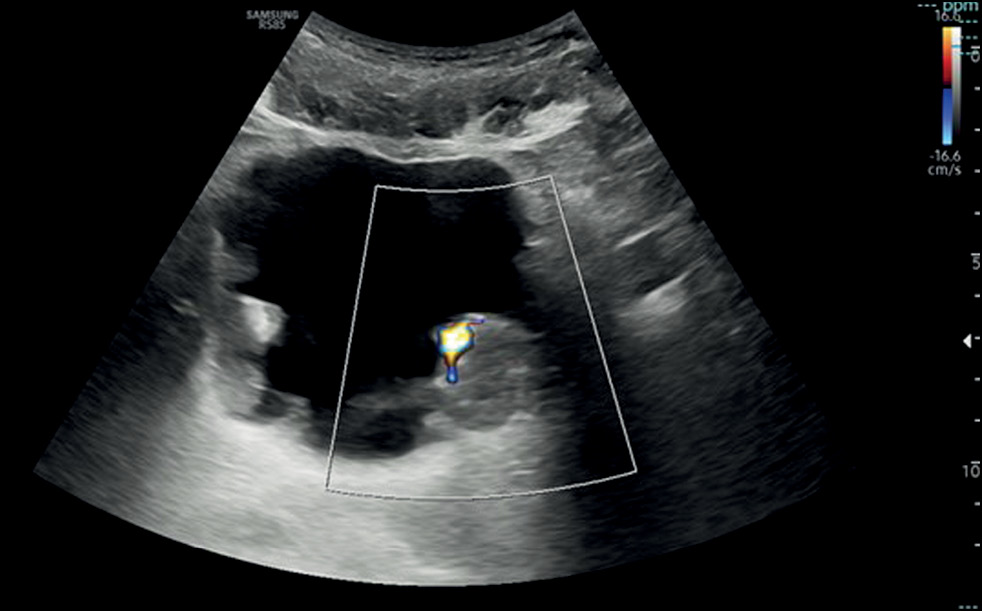

Этиология situs inversus totalis до сих пор не ясна, однако это состояние часто протекает бессимптомно, особенно у младенцев, и иногда ассоциируется с другими синдромами. Наша пациентка поступила в отделение неотложной помощи с болью в левом боку, тошнотой и лихорадкой. При первом ультразвуковом исследовании было выявлено нетипичное расположение внутренних органов. По этой причине была назначена компьютерная томография с контрастированием, после чего снимки были тщательно изучены. Ранее пациентка никогда не проходила компьютерную томографию, поэтому situs inversus totalis оказалась неожиданной и случайной находкой. При болях в груди или животе врачи могут предположить наличие situs inversus totalis по результатам компьютерной томографии, особенно если нет других клинических и визуализационных данных в анамнезе. Эти знания могут помочь в дифференциальной диагностике, позволяя избежать ненужных вмешательств. Более того, сопутствующие заболевания, затрагивающие несколько систем органов, в частности сердечно-сосудистую и лёгочную, встречаются у многих пациентов с situs inversus totalis, что требует тщательного обследования и наблюдения за ними в течение всей жизни.

370-378